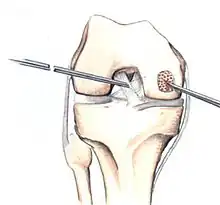

Intact lesions

If non-surgical measures are unsuccessful, drilling may be considered to stimulate healing of the subchondral bone. Arthroscopic drilling may be performed by using an antegrade (from the front) approach from the joint space through the articular cartilage, or by using a retrograde (from behind) approach through the bone outside of the joint to avoid penetration of the articular cartilage. This has proven successful with positive results at one-year follow-up with antegrade drilling in nine out of eleven teenagers with the juvenile form of OCD,[53] and in 18 of 20 skeletally immature people (follow-up of five years) who had failed prior conservative programs.[54]